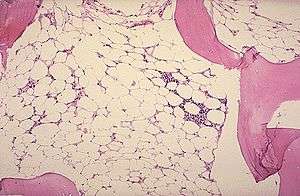

Micrograph of bone marrow taken from a patient with aplastic anemia | |

The definitive diagnosis is by bone marrow biopsy; normal bone marrow has 30–70% blood stem cells, but in aplastic anemia, these cells are mostly gone and replaced by fat.[2][3]